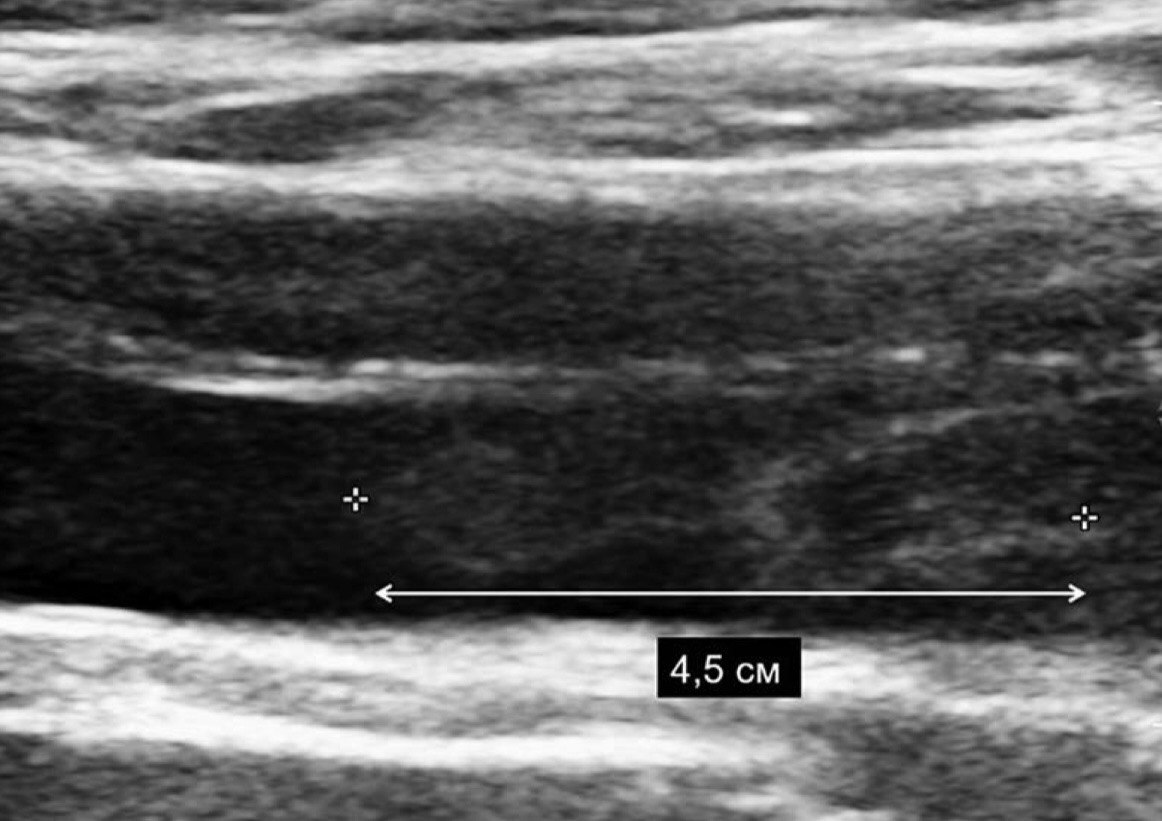

Ко мне на амбулаторный приём обратился пациент 40 лет с жалобами на увеличение в объёме левой нижней конечности. Нога ниже колена стала отекать пару недель назад, особенно после бега, а бегает он каждый день. Провоцирующий фактор выявить не удалось, получается "на ровном месте". Травм не было, длительных перелётов тоже. Пациент спортсмен, бегает марафоны, правильно питается, не имеет лишнего веса и вредных привычек, не принимает никаких препаратов на постоянной основе. Так же отмечает, что в последнее время появилась одышка при привычной физической нагрузке (плохой звоночек). При осмотре меня насторожила синюшная, отёчная голень, болезненная при пальпации (ощупывании руками). Приглашаю на УЗИ, ставлю датчик в проекции глубоких вен, и сразу бросается в глаза огромный тромб от голени почти до паха, болтающийся в просвете вены. Боюсь лишний раз надавить датчиком, чтобы от тромба не оторвался кусок и не полетел в лёгкие. (У каждого есть история, где у какого-то знакомого тромб "оторвался"). Крайне неприятная ситуация и для пациента и для врача. Удивляюсь, как пациент с таким огромным тромбом бегал ежедневно, ведь любая из этих пробежек могла стать для него последней. Говорю, что с такой картиной нужна госпитализация, пациент отказывается, ведь ничего особо не болит! Объясняю, что в любой момент может случиться "отрыв" и Бог знает, чем это закончится. Всё-таки всеми правдами и неправдами удаётся убедить молодого мужчину, что нужно ехать в больницу. Вызываю 103, бригада через 10 минут на пороге клиники, без разговоров забирают.